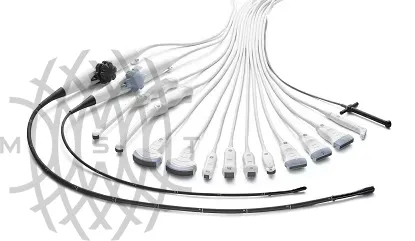

Доступные датчики УЗИ

Линейные датчики

9L-RS Linear Array Probe - 2,0 - 10,0 МГц, линейный мультичастотный датчик. Клиническое применение: ангиология (глубокие сосуды), педиатрия, скелетно-мышечная система, поверхностно расположенные органы.

12L-RS Linear Array Probe - 4,0- 13,0 МГц, линейный мультичастотный датчик. Клиническое применение: ангиология, поверхностно расположенные органы, педиатрия, скелетно-мышечная система.

ML6-15-RS Matrix Linear Array Probe - 5,0 - 15,0 МГц, высокочастотный матричный линейный мультичастотный датчик. Клиническое применение: поверхностно расположенные органы и структуры, скелетно-мышечный аппарат, периферические сосуды, педиатрия.

L4-20t-RS XDClear Linear Array Probe - 4,0 - 20,0 МГц, высокочастотный монокристальный линейный мультичастотный датчик. Клиническое применение: поверхностно расположенные органы и структуры, скелетно-мышечный аппарат, периферические сосуды, педиатрия.

L8-18i-RS Linear Array Probe - "4,5 - 18,0 МГц, Интраоперационный линейный мультичастотный L-образный датчик. Клиническое применение: Интраоперационные исследования, Ангиология, Поверхностно расположенные органы, Скелетно-мышечная система.

Фазированные датчики

M5Sc-RS Matrix Single Crystal Phased Array Probe - 1,5 - 4,6 МГц, матричный монокристальный секторный фазированный датчик. Клиническое применение: Взрослая кардиология, транскраниальные исследования.

6S-RS Sector Phased Array Comfort Scan Probe - 2,0 - 7,0 МГц, секторный фазированный мультичастотный датчик. Клиническое применение: Детская Кардиология, транскраниальные исследования.

12S-RS Sector Phased Array Comfort Scan Probe - 4,2 - 12,0 МГц, секторный фазированный мультичастотный датчик. Клиническое применение:Кардиология у новорожденных и детей, нейросонография.

Чреспищеводные датчики

6Tc-RS Multiplane Cardiac TEE Probe - 3.0-8.0 МГц, мультиплановый чреспищеводный датчик для взрослых. Клиническое применение: Чреспищеводные исследования сердуа у взрослых.

9T-RS Multiplane Cardiac TEE Probe - 3,6 - 10,0 МГц, мультиплановый чреспищеводный датчик

Клиническое применение: Чреспищеводные исследования сердца у детей.

Конвексные датчики

C1-5-RS Convex - 1,5 - 5,0 МГц, мультичастотный конвексный датчик. Клиническое применение: брюшная полость, акушерство и гинекология, урология, ангиология.

4C-RS Convex Curved Array Probe - 1,5 - 5,0 МГц, мультичастотный конвексный датчик. Клиническое применение: брюшная полость, акушерство и гинекология, урология, ангиология.

8C-RS Micro-Convex Probe - 3,5-10,0 МГц, Мультичастотный микроконвексный датчик.

Клиническое применение: педиатрия - нейросонография, брюшная полость, урология, ангиология, скелетно-мышечная система.

E8C-RS Micro-Convex Endocavity Probe - 3,5-10,0 МГц, мультичастотный внутриполостной микроконвексный датчик. Клиническое применение: акушерство и гинекология, урология.

E8Cs-RS Microconvex - 3,5-10,0 МГц, Мультичастотный внутриполостной микроконвексный датчик. Клиническое применение: акушерство и гинекология, урология.

Карандашные допплеровские датчики

P2D CW Doppler Pencil Probe - 1,9-2,1 МГц карандашный допплеровский датчик. Клиническое применение: кардиология.

Датчики

Передовая технология компании GE, используемая при производстве датчиков, помогает добиться исключительного качества изображения. Она применяется для широкого спектра датчиков, разработанных с учетом особенностей проведения различных исследований.